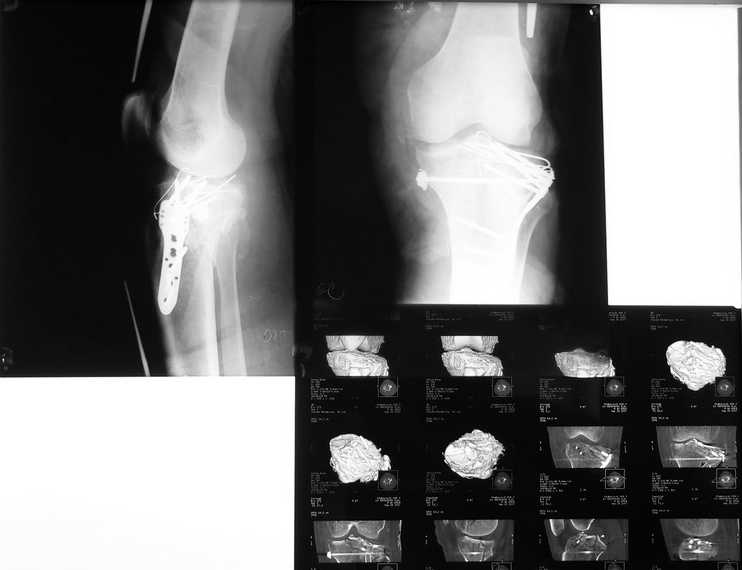

Мыщелки голени

Результат после операции

R-гр контроль и КТ после синтеза межмыщелкового перелома голени. Первичные снимки в сообщении от 20 сентября. Критика коментарии приветствуются. С уважением Пак Л.